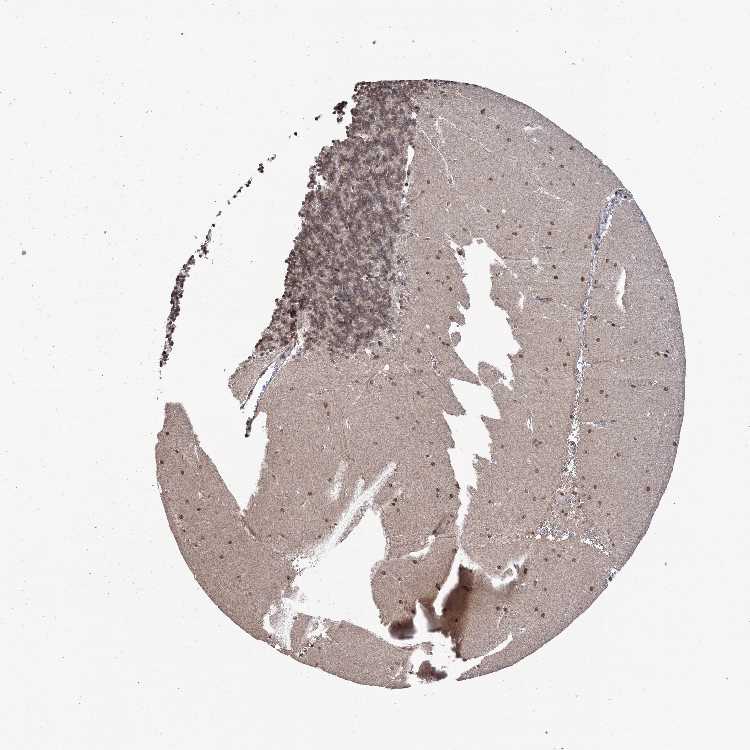

CEREBELLUM - Antibody stainingi

Antibody staining in the annotated cell types in the current human tissue is reported as not detected, low, medium, or high, based on conventional immunohistochemistry profiling in selected tissues. This score is based on the combination of the staining intensity and fraction of stained cells.

Each image is clickable and will lead to virtual microscopy that enables deeper exploration of all samples and also displays staining intensity scores, fraction scores and subcellular localization as well as patient and tissue information for each sample.

Antibody HPA038854

Purkinje cells Medium

Cells in granular layer Low

Cells in molecular layer Medium